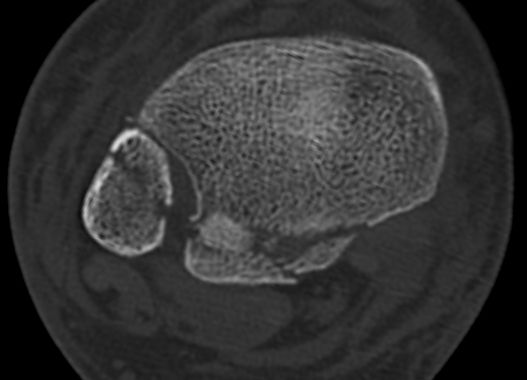

Today’s monteggia brought to you by the CCCP

#orthosky

#orthopedics

December 11, 2024 at 12:39 PM